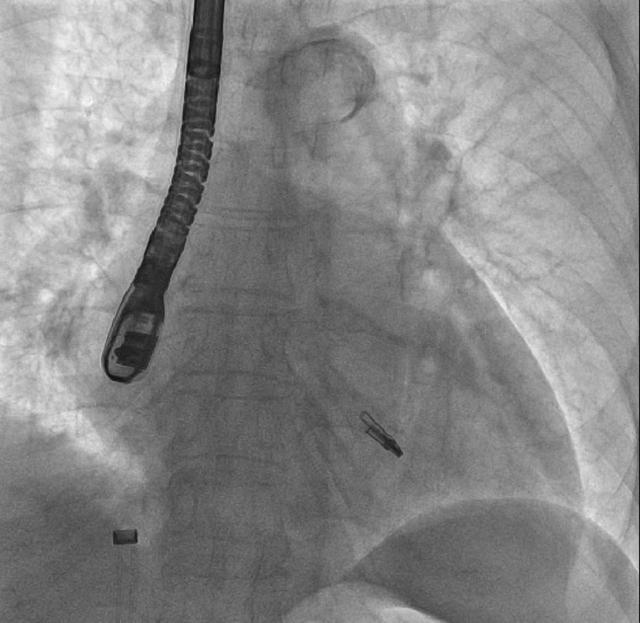

钳子DSA影像